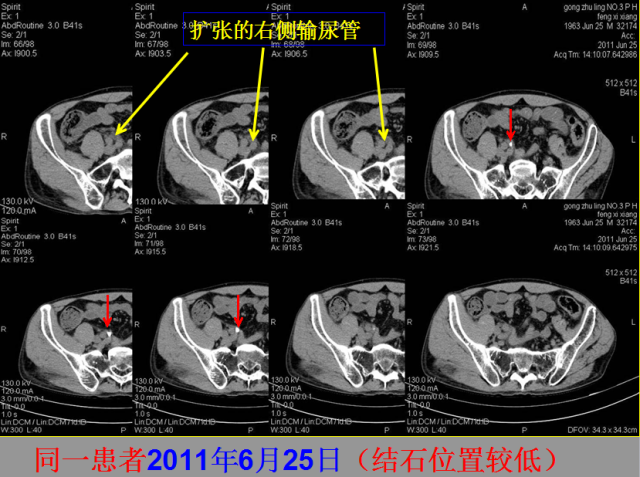

05